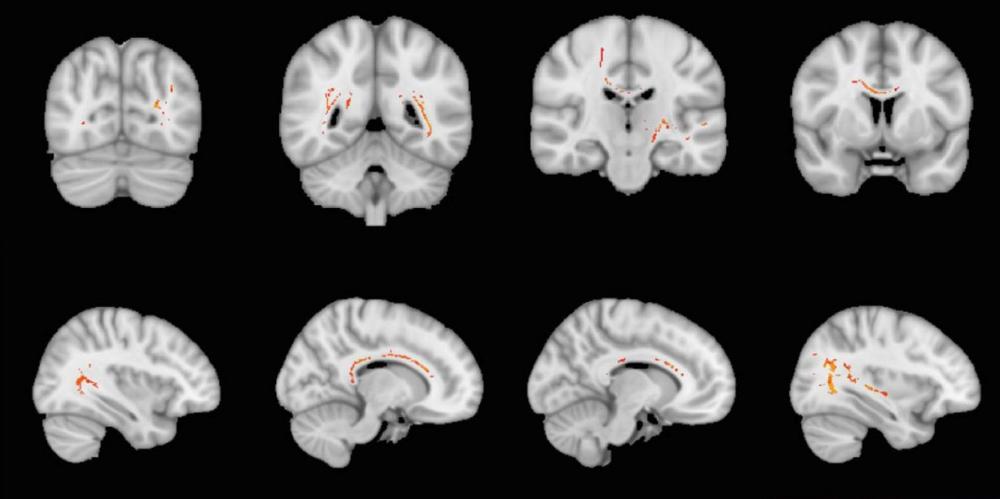

The wiring network in the brain was not better preserved in the Generation 100 groups that were offered organized exercise, compared with the participants who were advised to exercise on their own. Nevertheless, the results suggest that high fitness and high-intensity training are beneficial for maintaining better structure in this network.

Good signaling in the brain depends on intact nerve fibers and a thick layer of myelin that insulates these fibers. Together, nerve fibers and myelin form the white matter of the brain. In this study, we used MRI to examine the structural organization of white matter in 105 of the 70-77 year old participants in the Generation 100 project. The measurements were made at start-up and after one, three and five years of exercise follow-up, respectively.

Myelin ensures that molecules move along the nerve fibers instead of diffusing away from the fibers. A high degree of myelination therefore indicates good conduction capacity of nerve signals in the brain. Our results show that elderly people with high exercise capacity - in all three groups - had both a greater degree of myelinated nerve fibers and of molecules that moved along the nerve fibers. However, this correlation was strongest at start-up and after one year, and decreased after that.

The study also found a link between higher self-reported exercise intensity and better structure of the white matter of the brain. Here, too, the association was only present at the beginning of the study period. The results may be an indication that high-intensity training and high fitness protect against damage to the wiring in the brain in the elderly. At the same time, it may seem that this effect diminishes as one approaches 80 years.

In general, the findings agree well with other results on exercise and brain health from the Generation 100 project (see here, here, here, here and here).

The Generation 100 study showed no effect of organized exercise follow-up on avoiding age-related changes in the structure of different parts of the brain. On the other hand, the participants who started the study with high aerobic capacity had better preserved structural complexity of cerebral gray matter - and specifically in the temporal lobe - compared with those who were less fit.

Better maintenance of fitness throughout the five years of the study was also associated with better preserved structure in the temporal lobe. This area of the brain is sensitive to physiological aging and the development of Alzheimer's disease.

In Generation 100, three groups of older women and men exercised differently, with two of the groups being offered organized exercise twice weekly. This substudy includes the 105 participants who underwent MRI scans of the brain before and during the study. A new method was used to assess structural complexity more accurately in different parts of the brain.

After five years, the measurements of structural complexity showed equal reductions in all three exercise groups. But a high maximum oxygen uptake was linked to better preserved complexity in parts of the cerebrum. The level of fitness had, however, no effect on the thickness of the cerebral cortex.

The results are largely reminiscent of other recently published findings on exercise and brain health based on the Generation 100 study. The general conclusion seems to be that high age-related fitness can be a key to maintaining important brain functions and avoiding wasting of brain tissue for the elderly.

We found no beneficial effect of high fitness or long-term organized exercise on the development of white spots in the brain of older adults. These spots can be seen on MRI, and are common after the age of 50. The spots are scars in the wiring in the brain, and are associated with impaired gait function, cognitive impairment, depression and stroke. Neither in the participants who were offered organized interval training with high intensity, nor in those who could attend moderate training sessions, did the growth of these scars develop differently than in those who exercised on their own.

The study includes 105 of the participants in the Generation 100 study. Their brains were checked with MRI before, during and after the five-year exercise period. The extent of white spots increased in all three groups, especially during the last couple of years of the 5-year period. The other three studies we have published on brain health in the Generation 100 study show that high fitness protects against cognitive impairments. However, we found no association between fitness and the development of white spots. Nor did those who improved their fitness during the study have slower development of white spots in the brain than the rest of the participants.

Organized exercise follow-up did not prevent loss of brain cells compared to giving general exercise advice without offering organized exercise sessions. However, Generation 100 participants with high cardiorespiratory fitness at the onset of the study had thicker cerebral cortex throughout the five-year exercise period than those who were less fit.

To check for changes in brain volume and the thickness of the cerebral cortex, we performed MRI scans of the brains of 105 of the 70-77 year old participants in the Generation 100 study both before, during and after the exercise intervention. The group that exercised on their own without organized follow-up had less than age-expected atrophy of the hippocampus and the foremost part of the brainstem. In the groups exercising at high and moderate-intensity, respectively, the atrophy was somewhat greater than among those who exercised on their own, but still not higher than what is expected for people in their 70s.